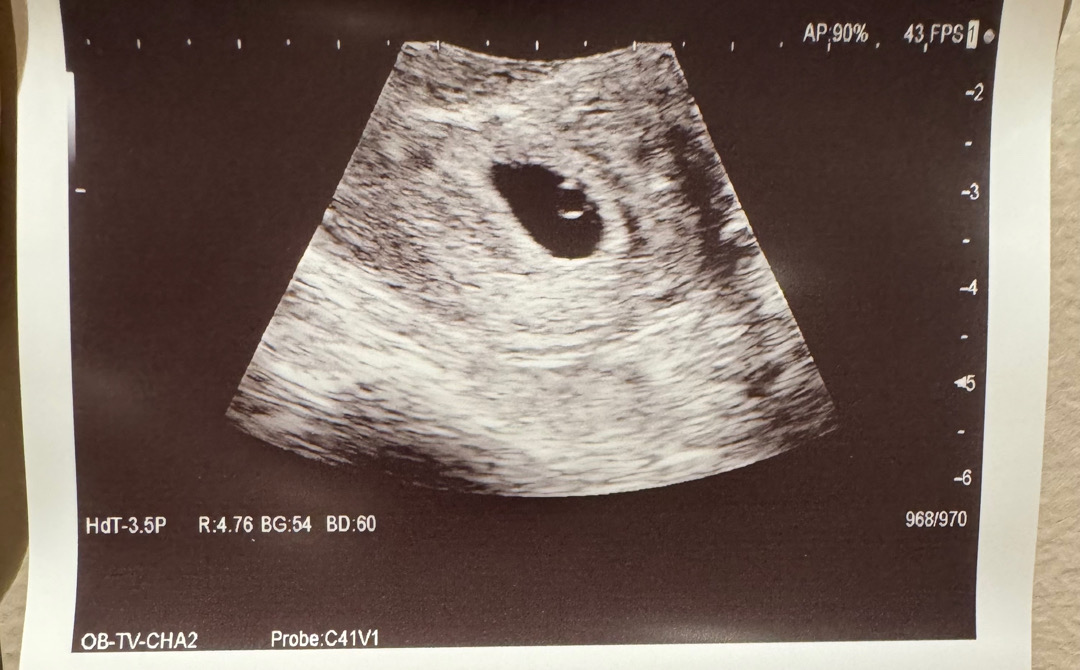

아기집 난황보고 왔어요

5주 4일 아기집 난황 까지 보고왔어요 근데 가슴통증이 하루아침에 사라져서 걱정이 되네요 배통증도 밤에만 있고 또 낮에는 없어요 증상이 있어도 걱정 없어도 걱정 되네요 좋은생각만 해야겠죠?

원래 아기집 난황 아기 순이자나요 다음주에 심소 들으러 갈때 보려구요

아 그런가요? 저희도 아기집 난황까지 봤는데 아기는 아직 안보인대서 너무 걱정했거든요ㅜㅜ